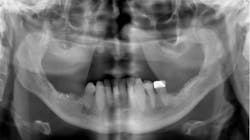

Alternatives for care (figure 1)

A patient who has some restorable teeth remaining, controllable periodontal disease, and no interest in dental implants should be able to have either of these procedures done, if financial resources are available. The only major decisions are the materials used for the restorations and whether to use fixed or removable prostheses.